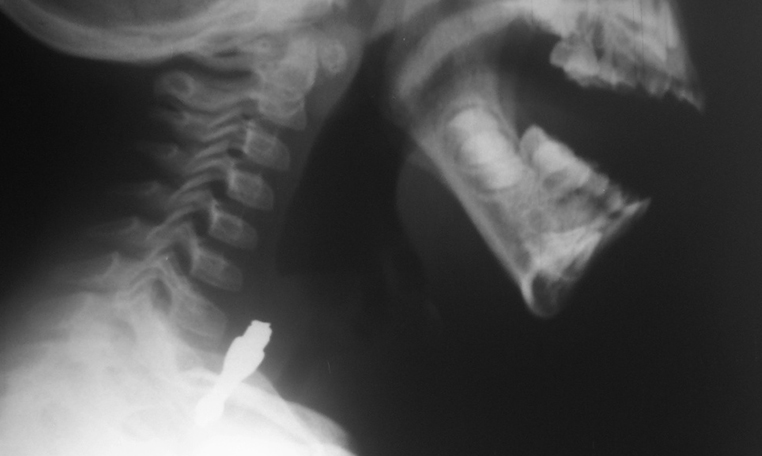

Cuerpo Extraño en Esofago